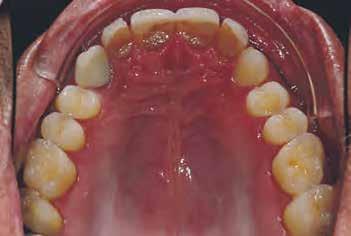

gyorsan és költség - Dr. Miguel Stanley, dr. Ana Gomes Paz, dr. Inês Miguel (Portugália) Dr. Christian Coachman (Brazília) 1. ábra: Kiindulási állapot (frontális irányból). 2. ábra: A kiindulási állapotról okkluzális irányból készített felvétel (felső állcsont). 3. ábra: A kiindulási állapotról okkluzális irányból készített felvétel (alsó állcsont). 4. ábra: A kiindulási állapotról készült panorámaröntgen felvétel (2015).

Esetbemutatás

2015-ben egy 47 éves férfi páciens állkapocs-ízületi panaszai miatt kereste fel a rendelőnket. Ezen felül esztétikai problémát jelentett számára, hogy az egyik felső nagymetszőfogán lévő héj eltört (1-3. ábrák). A klinikai és radiológiai vizsgálatot követően megállapítható volt, hogy a páciens kifejezett bruxizmusa miatt csökkent a harapási magassága, és jelentős mennyiségű saját foganyagot abradált el (4. ábra)